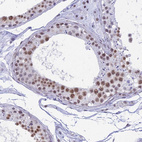

Immunohistochemical staining of human fallopian tube shows moderate nuclear positivity in glandular cells.